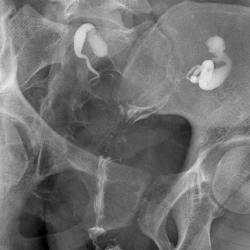

Hystérosalpingographie

Sous contrôle radiologique, le médecin placera une sonde dans l'utérus. Ensuite, pour étudier la morphologie de l'utérus et des trompes, il injectera un contraste radio-opaque.